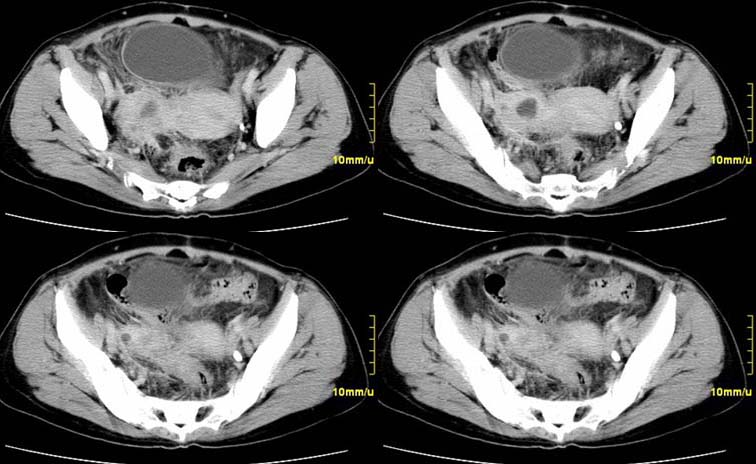

患者,52,右下腹疼痛一月,当时有发热,抗炎治疗20余天,至今仍疼痛,且有低热。

增强

右附件区软组织包块,内囊变坏死,边缘模糊,与子宫,与膀胱分界不清,增强强化与子宫密度相近.盆腔内无肿大淋巴结考虑炎性包块可能性大。

右附件区软组织包块,内可见坏死,边界不清,周围软组织及脂肪组织可见密度增高,膀胱右侧壁增厚,并且呈膨胀不全的改变,考虑炎性包裹,不知道有没有手术史??

临床特点:

右下腹疼痛一月,当时有发热,抗炎治疗20余天,至今仍疼痛,且有低热,具有典型炎症的临床表现。

ct表现:

右侧附件见一肿块,边缘与周围组织分界不清,增强扫描见肿块明显强化,越到后期强化越明显,中央见坏死,内壁光整,与临近子宫壁、直肠及膀胱后壁均见炎症波及。这种厚壁肿块、内缘光整外缘模糊、增强扫描强化越后越强是附件脓肿典型的ct表现。

诊断:

右侧卵巢输卵管慢性脓肿,炎症波及临近子宫、直肠及膀胱形成粘连。